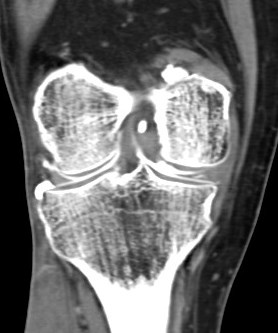

68 yo male with medial knee pain and a pacemaker.

Figure 3 for case Medial meniscus tear ( RID2772 )

Figure 3

Oblique tear of the medial meniscus shown on a CT arthrogram.

Medial meniscus tear ( RID2772 )